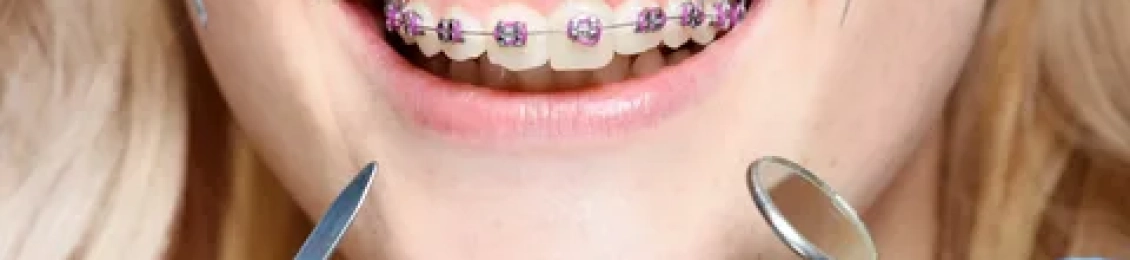

يعاني العديد من الأشخاص من مشكلة الأسنان البارزة ويكون التقويم هو الحل الأفضل للتخلص من هذه المشكلة، ولذلك يتساءل البعض عن مدة تقويم الأسنان للحالات البسيطة حيث تختلف فترة التقويم من شخص إلى آخر، ومن هنا نجد أن مجمع الطب المتميز في المدينة المنورة يوفر لك أفضل أنواع التقويم بأقل الأسعار كما تتم الخدمات على […]

يبحث الكثير عن نتائج التقويم قبل وبعد التى تظهر الفارق الكبير في تحسين الابتسامة وصحة الفم بشكل عام، ونتيجة لهذه الحالات فإن التقويم لا يقتصر على الجانب التجميلي بل يصلح عيوب الفكين مثل التزاحم والفراغات وبروز الأسنان، بالإضافة إلي أنه يظهر انتظام أفضل للأسنان يحسن المضغ والنطق ويقلل مشاكل اللثة والتسوس، ومن هذا المنطلق يبرز […]

الهدف من تركيب تقويم الاسنان هو إظهار الشكل الجمالي للفم وعلاج مشاكل الأسنان في الوقت ذاته، ولكن يجب أن تعرف متى يوضع تقويم الأسنان وأفضل الأنواع لاختيار النوع المناسب لك وسوف يساعدك مجمع الطب المتميز على ايجاد كل ما تبحث عنه حيث لديه نخبة من أفضل الأطباء المتخصصين في طب الأسنان كما يوفر لهم أفضل […]